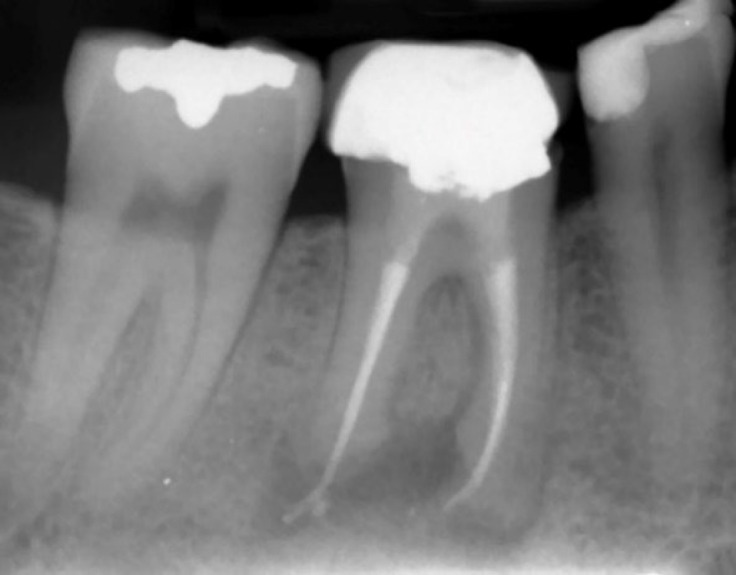

本病例报告旨在记录一名 35 岁男性患者的罕见远端牙源性病变,该患者下颌右侧第一磨牙有轻微的临床不适;探讨了不常见的远端牙髓病变的诊断和治疗的复杂性,最终通过细致的非手术再治疗得到了解决。尽管口腔检查结果正常,但放射诊断检查却显示根管治疗效果不佳,根尖中、远端病变环绕根尖;包括通过全景放射检查发现的下颌第二磨牙根尖下方的明显放射线,并经锥形束计算机断层扫描证实。此外,计算机断层扫描还发现了一个以前从未报道过的、异常巨大的牙髓病变,该病变向下颌管延伸;这凸显了继续探索这一独特牙髓病变的必要性。非手术的牙髓再治疗使放射状病变在一年内显著缩小;强调了综合诊断方法和个体化治疗的重要性。

The current case report aims to document a rare presentation of a distant odontogenic lesion of a 35-year-old male patient with mild clinical discomfort in the mandibular right first molar; exploring the diagnostic and therapeutic intricacies of an uncommon distant endodontic pathosis ultimately resolved through meticulous nonsurgical retreatment. Despite a normal oral examination, diagnostic radiography revealed a suboptimal root canal treatment and apical lesions surrounding mesial- and distal-root apices; including a distinct radiolucency beneath the apex of the second mandibular molar discovered through panoramic radiography, and confirmed via cone-beam computed tomography. In addition, the computed tomography disclosed a previously unreported and unusually large endodontic lesion that extended toward the mandibular canal; highlighting a necessity for the continued exploration of a unique endodontic presentation. A nonsurgical endodontic retreatment led to a remarkable reduction in the radiolucent lesions within one year; emphasizing the significance of comprehensive diagnostic approaches and individualized treatments.